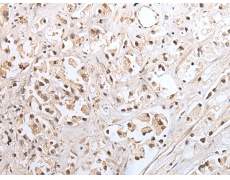

ELISA, IHC |

IHC positive control: |

Human gastric cancer and human prostate cancer |

IHC Recommend dilution: |

25-100 |